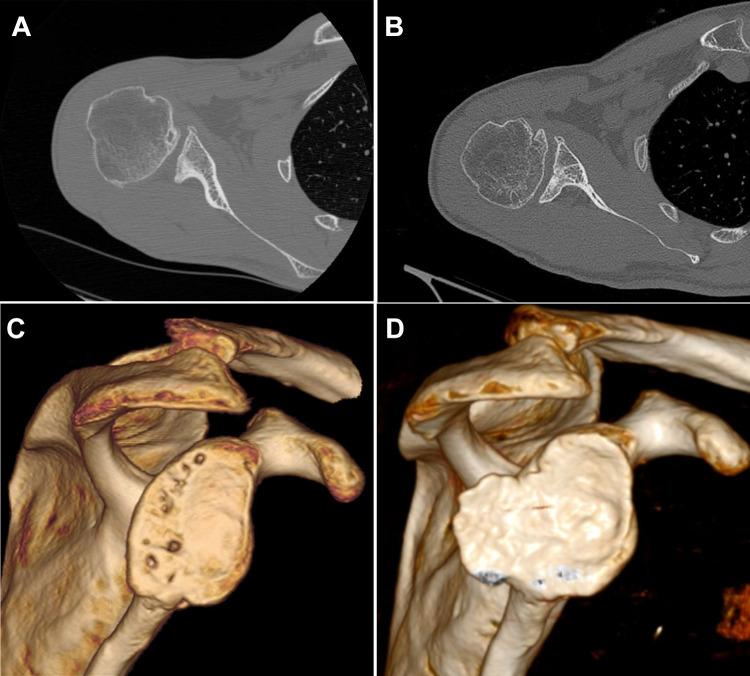

Restoration of the Posterior Glenoid in Recurrent Posterior Shoulder Instability Using an Arthroscopically Placed Iliac Crest Bone Graft: A Computed Tomography-Based Analysis.

Patients with preoperative CT scans and at least 2 postoperative CT scans with a minimum follow-up of 2 years were included in the evaluation. Of 49 initial patients, 17 (follow-up rate, 35%) met the inclusion criteria and were available for follow-up. We measured the glenoid version angle and the glenohumeral and scapulohumeral indices on the preoperative CT scans and compared them with measurements on the postoperative CT scans. Postoperatively, graft surface, resorption, and defect coverage were measured and compared with those at early follow-up (within 16 months) and final follow-up (mean ± SD, 6.6 ± 2.8 years).

The mean preoperative glenoid version was -17° ± 13.5°, which was corrected to -9.9° ± 11.9° at final follow-up ( < .001). The humeral head was able to be recentered and reached normal values as indicated by the glenohumeral index (51.8% ± 6%; = .042) and scapulohumeral index (59.6% ± 10.2%; < .001) at final follow-up. Graft surface area decreased over the follow-up period, from 24% ± 9% of the glenoid surface at early follow-up to 17% ± 10% at final follow-up ( < .001). All clinical outcome scores had improved significantly. Progression of osteoarthritis was observed in 47% of the shoulders.

Arthroscopically assisted posterior ICBG restored reliable parameters as shown on CT scans, especially glenoid version and the posterior subluxation indices. Graft resorption was common and could be observed in all shoulders. Patient-reported clinical outcome scores were improved. Osteoarthritis progression in almost 50% of patients is concerning for the long-term success of this procedure.